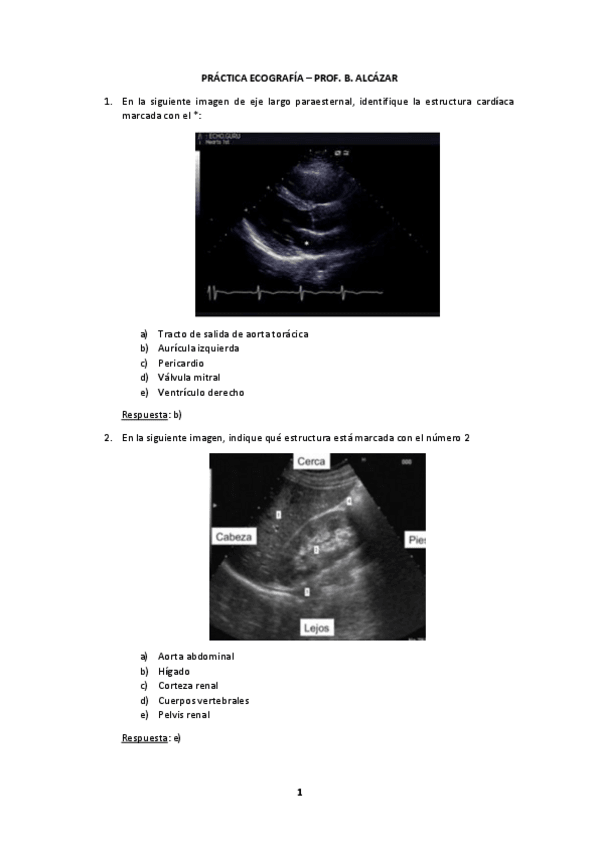

He publicado nuevos practicas de 3º Bases de la Medicina Interna II: evaluacion-ecografia.pdf

PRACTICA-ECOGRAFIA.pdf